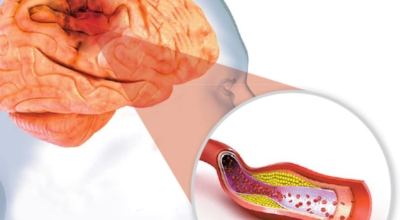

뇌졸중은 뇌경색과 뇌출혈 두가지로 나뉘게 됩니다. 먼저 뇌경색은 뇌혈관이 막혀 영양분과 산소를 주는 피가 통하지 않는 상태로 원은은 크게 세 가지로 나눌 수 있는데요 동맥경화증이 생겨 좁아진 부위로 인해서 혈액공급이 부족해지거나 좁아지다가 결국 막혀버리는 경우, 큰 혈관에서 분지한 작은 혈관들이 고혈압 등으로 압박을 받으면 혈관이 막히는 경우가 있어요.

또한 심장 판막질환이나 심방세동 또는 심근병 등의 심장 질환이 있는 경우 심장에서 혈전이 만들어지고 그게 뇌로 흘러가게 되면 뇌혈관을 막게 되는 경우가 있습니다. 뇌출혈은 뇌경색과 반대로 뇌혈관이 터져서 발생하는 뇌내 출혈과 거미막하 출혈로 나누게 되어요. 거미막하출혈은 혈관벽의 약한 부분이 부풀어 오르는 뇌동맥류가 터지는 경우와 연관성이 크다고 합니다.